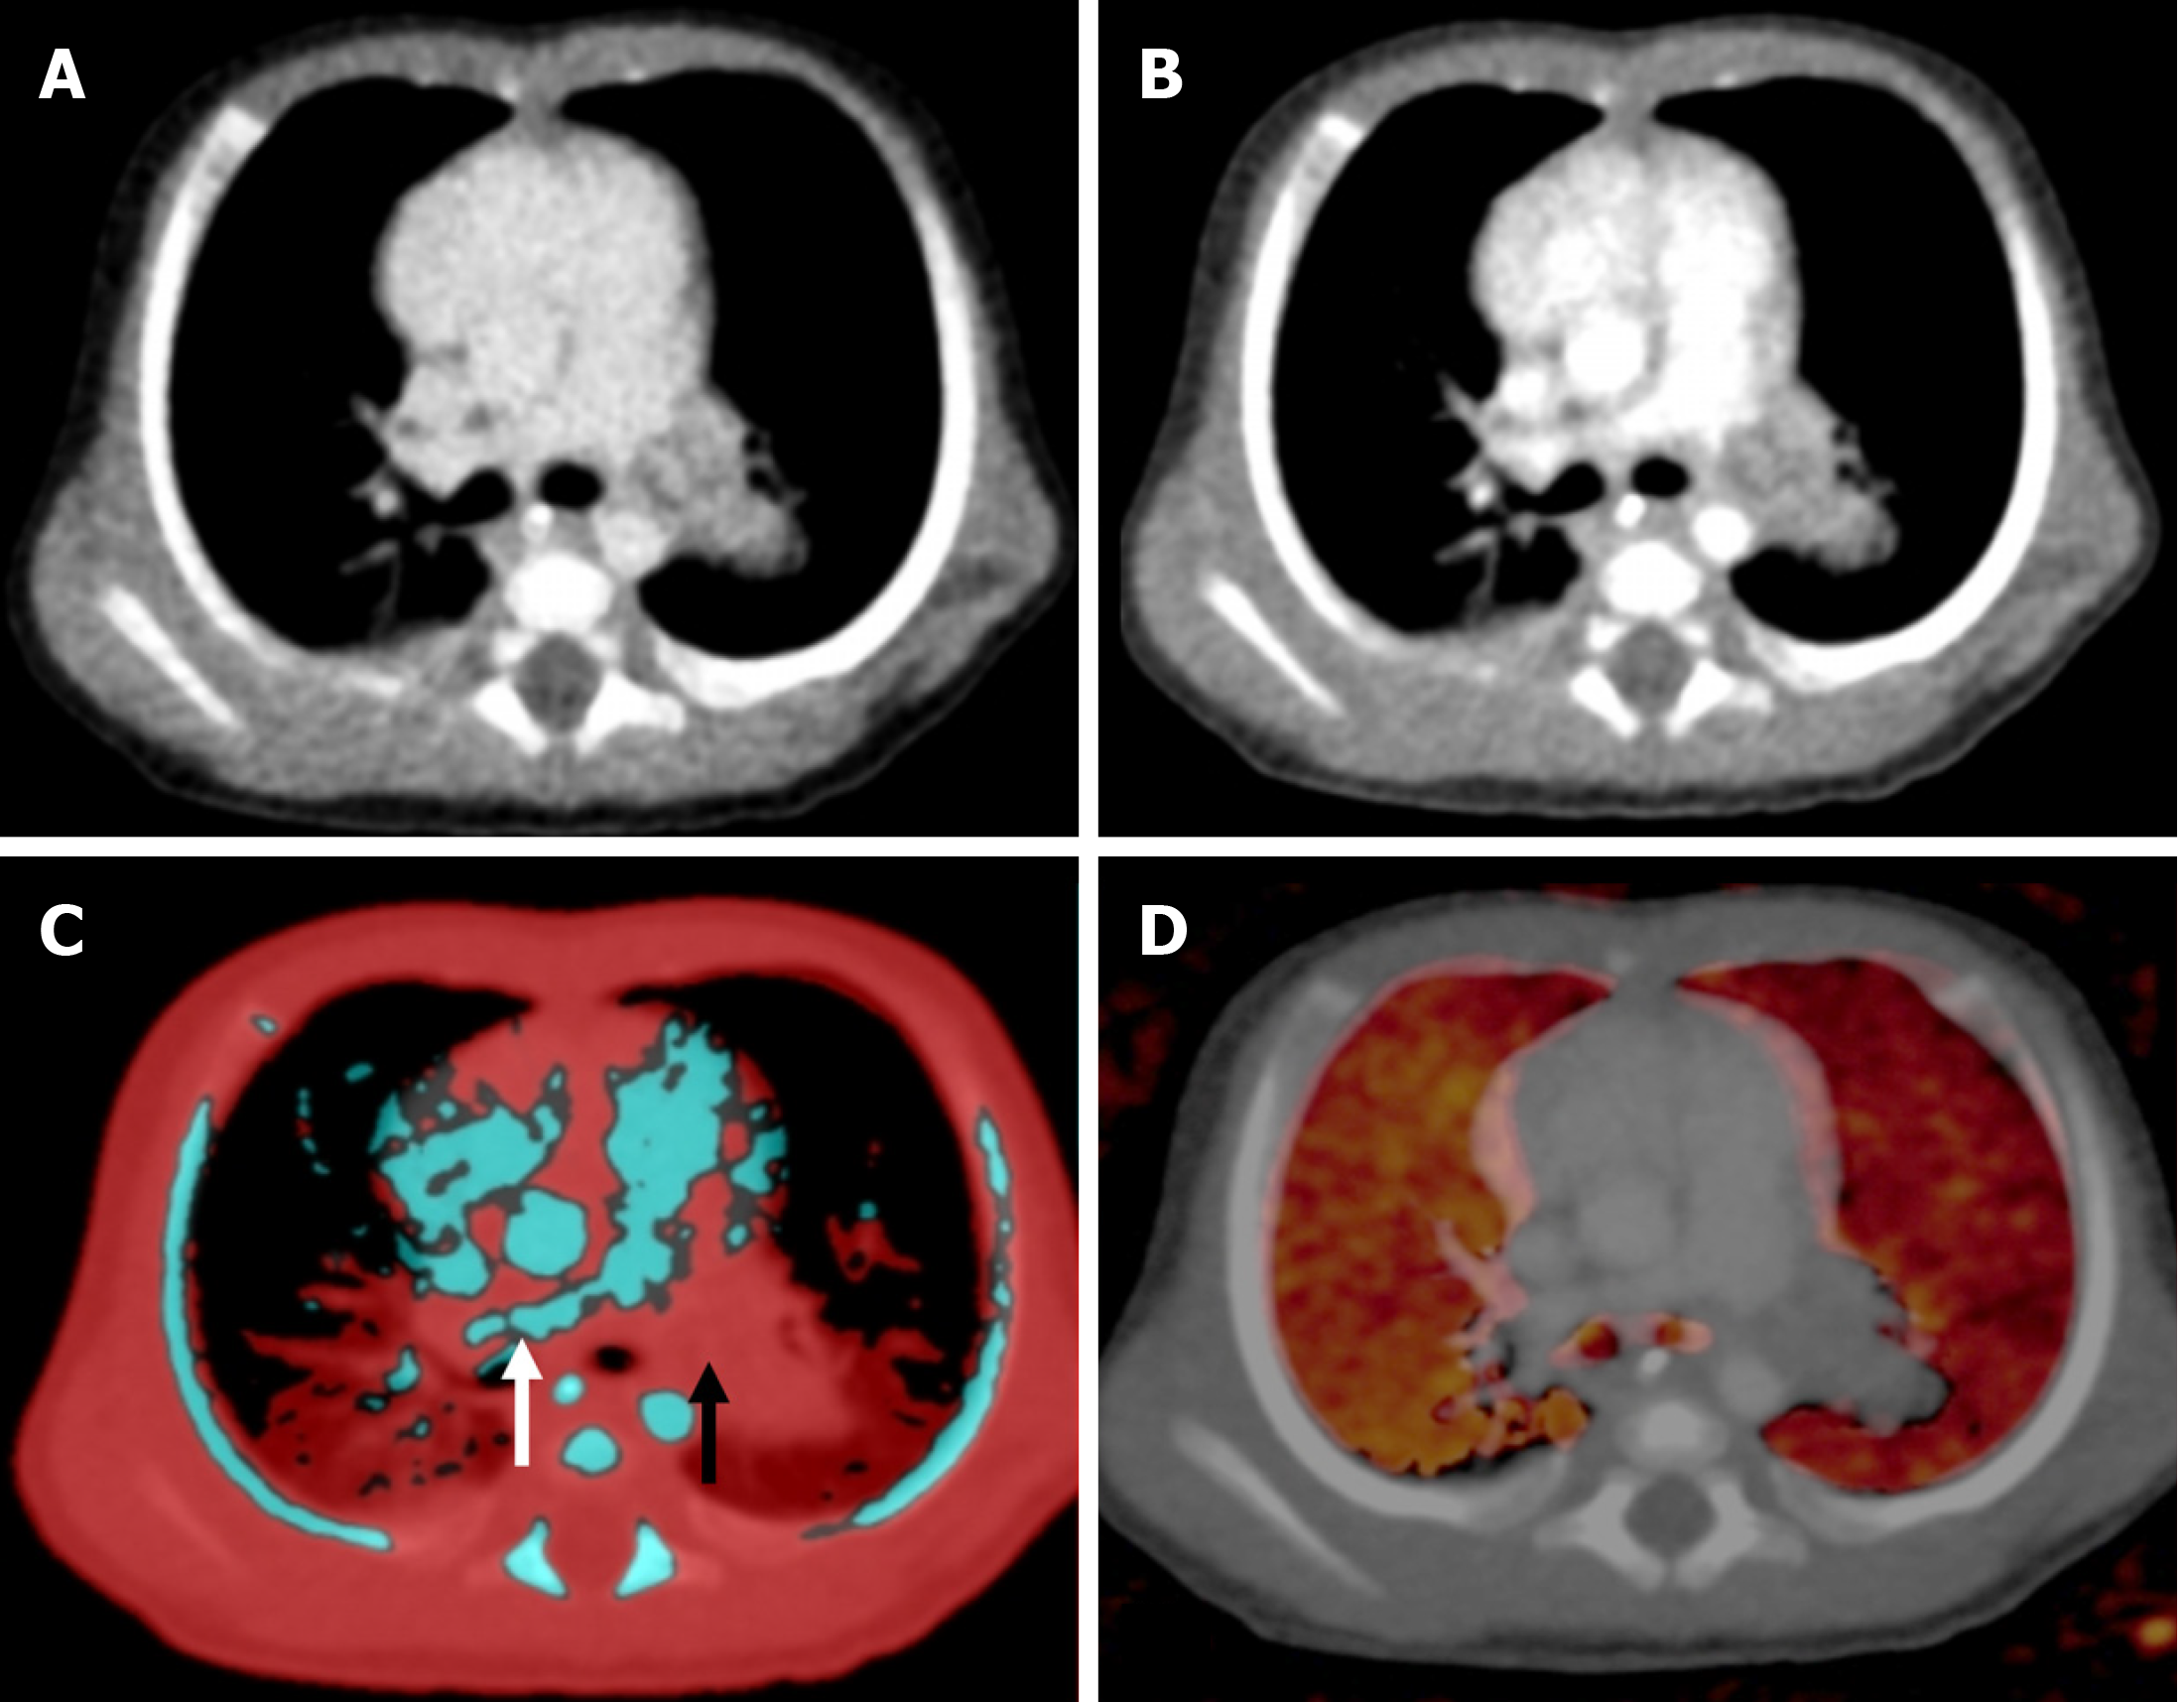

Figure 7 A 4-year-old male with hemophilia A who presented with acute headache and neck rigidity.

A: Axial mixed-enhanced CT head images showed subtle extra-axial high-density lesions (indicated by arrows) in the left frontal and parietal lobes, resulting in a slight midline shift to the opposite side; B: The virtual non-contrast image confirmed that the hyperdensity (arrows) represented an acute bleed and not abnormal enhancement; C: Bone removal tool of dual energy demonstrated the bleed more clearly (arrows); D: Iodine overlay image did not show any iodine uptake in the region of the bleed.